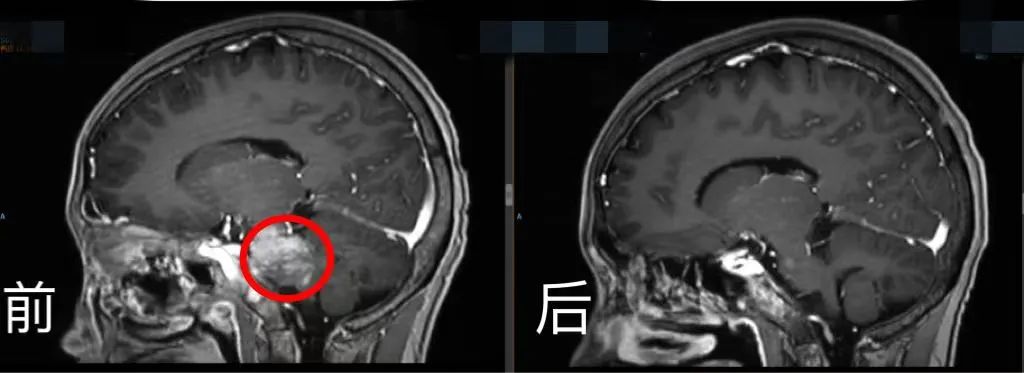

此時(shí),小玉身體里的腫瘤轉(zhuǎn)移到腦部,腫瘤又變得猖獗。病情加重時(shí),小玉再次暴瘦。血腦屏障的存在導(dǎo)致大多數(shù)藥物難以進(jìn)入大腦。如何突破這一難題?

腦部CT前后對(duì)比。四川省腫瘤醫(yī)院供圖

林桐榆領(lǐng)銜腫瘤內(nèi)科、重癥醫(yī)學(xué)科、放療科、影像科、病理科和營(yíng)養(yǎng)科等多學(xué)科治療團(tuán)隊(duì),通過(guò)多學(xué)科個(gè)體化的方式,根據(jù)病理結(jié)果及靶點(diǎn)反復(fù)為小玉研究個(gè)體化的抗腫瘤治療,“一邊大劑量用藥,一邊降低毒性、盡量減少副作用?!?/p>

雖然一個(gè)問(wèn)題接著一個(gè)問(wèn)題,治療團(tuán)隊(duì)始終不拋棄、不放棄,借助分子病理技術(shù)不斷地去分析靶點(diǎn),冒著風(fēng)險(xiǎn)實(shí)施大劑量藥物治療,還采用了川腫最新引進(jìn)的全球最先進(jìn)的射波刀等治療手段,全院力量聚焦,為一個(gè)生命努力。

經(jīng)院內(nèi)多學(xué)科MDT討論,團(tuán)隊(duì)制定出同步放化療的橋接治療及后續(xù)CAR-T細(xì)胞治療的方案。在密集的化療及放療等橋接治療后,復(fù)查影像學(xué)提示病灶明顯縮小,骨髓穿刺涂片、流式及活檢均未見(jiàn)腫瘤累及。按照CAR-T細(xì)胞治療流程,小玉接受了單采、預(yù)處理及CAR-T細(xì)胞回輸?shù)忍幚?。CAR-T細(xì)胞治療用好了有可能提高治愈率,但它是一把雙刃劍,容易伴隨細(xì)胞因子釋放綜合征等副作用,引起免疫反應(yīng),特別是腦轉(zhuǎn)移者。一旦出現(xiàn)嚴(yán)重不良反應(yīng)將前功盡棄。

經(jīng)過(guò)2周的院內(nèi)嚴(yán)密監(jiān)測(cè)護(hù)理,小玉沒(méi)有發(fā)生細(xì)胞因子釋放綜合征和神經(jīng)相關(guān)毒性等不良反應(yīng),再次復(fù)查影像學(xué)病灶幾乎完全消失。